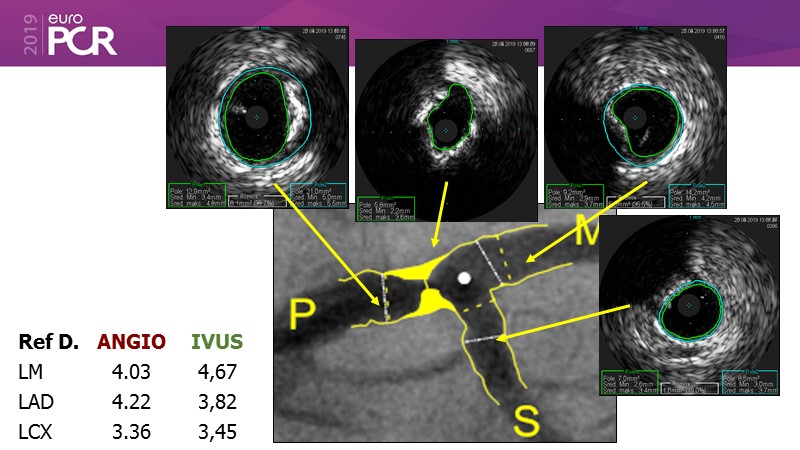

Distal left main stenosis: how to treat optimally with dedicated bifurcation stent BiOSS Lim C. Case-based session